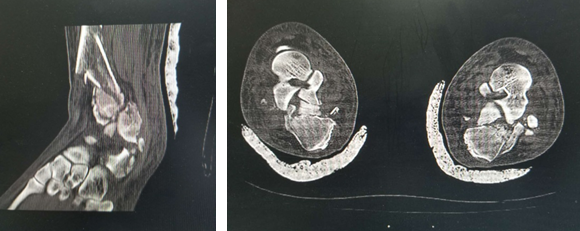

在必威官方首页官网betway,急诊医生给华大姐完善各项检查,发现她的伤情很严重:双pilon骨折,双跟骨骨折,腰椎多发骨折。急诊医生立刻联系足踝科徐明亮主任前来会诊,徐主任仔细检查了华大姐的病情,安排她先进行距骨牵引,消肿一周,等待合适的手术时机。

术前

“病人双侧跟骨粉碎性骨折,胫骨远端粉碎性骨折,受伤暴力大,周围软组织损伤也比较重,短时间内局部出现张力性水泡,早期切开后,一是容易导致伤口难以缝合,另外也增加了感染的机会,所以要在消肿以后,再给她切开复位内固定,减少患者伤口感染的几率。”徐明亮主任说。

消肿半个月,手术时机到来,正值同济大学附属同济医院足踝专家俞光荣教授来sararz坐诊,俞教授看到华大姐的复杂病情后很感兴趣,决定亲自主刀手术。